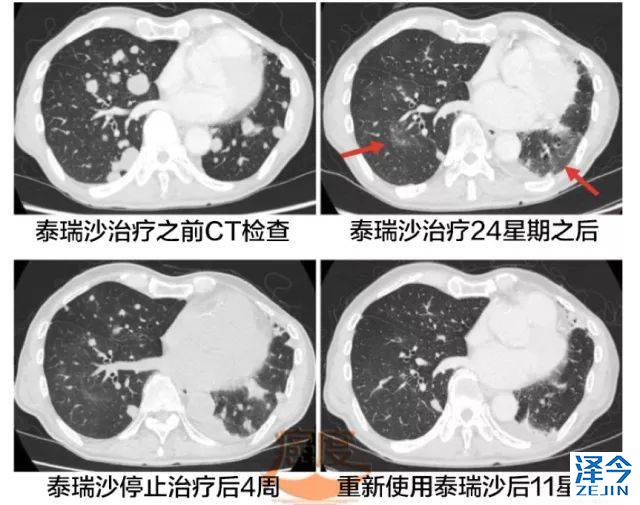

随着第十线的化疗结束之后,患者开始在2016年6月使用奥希替尼, 8周后病人进行全身CT和核磁检查,检查结果表明肺部病灶、脑转移灶急剧萎缩,使用奥希替尼24周(大概6个月),尽管全身的病灶仍在缩小,但是胸部CT显示肺下叶有两个无症状的磨玻璃影。

这个被认可可能是奥希替尼诱导的间质性肺炎(ILD),因此患者停止了使用奥希替尼。

停用奥希替尼四周之后,影像学检查显示病人双肺出现新的转移灶,但是病人肺部的毛玻璃阴影(GGO)只是轻度缓解。由于之前报道在奥希替尼治疗期间,出现这种频繁短暂的肺部不透明(TAPO),还是可以继续使用奥希替尼治疗。

重新使用泰瑞沙4星期后,胸部CT揭示出肺部多发结节的萎缩,同时血浆的肺腺癌相关抗原KL-6水平显著下降,从之前的911U/ml下降到664U/ml。

重新使用泰瑞沙11星期之后,全身的CT检查显示多发肺部结节减少。肺部的毛玻璃样阴影没有加重。